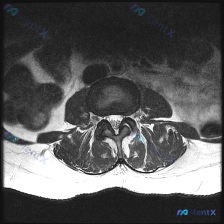

这是一张腰椎MRI的T2加权轴位图像,显示腰椎某节段横断面结构,结合形态判断大概率是L4/5或L5/S1这类腰椎好发受累节段,具体需要结合矢状位确认。

- 椎间盘:T2信号明显减低(呈黑色),没有正常髓核的高信号,提示椎间盘脱水退变;同时纤维环后缘有向后方的弥漫性膨出

- 椎管与神经:中央椎管矢状径明显变窄,呈典型的"三叶草"形态;硬膜囊明显受压,截面积减小,前缘受椎间盘压迫、后缘受黄韧带压迫;双侧侧隐窝也明显变窄

- 韧带与关节:双侧黄韧带增生肥厚,向椎管内突出;关节突关节面有骨质增生,关节间隙狭窄、形态不规则

- 多个结构的退变共同挤压,最终导致椎管明显狭窄,变成了典型的「三叶草」形态

- 支持点:所有影像发现都符合:椎间盘退变脱水+膨出、黄韧带肥厚、小关节增生,三个因素共同导致椎管狭窄,形成三叶草形态,是非常经典的表现;没有红旗征支持其他病因

结合现有影像信息,最符合的诊断是退行性腰椎管狭窄症,包含了腰椎间盘退行性变伴膨出、黄韧带增生肥厚、关节突关节骨质增生三个核心病理改变。临床后续需要结合患者症状、体格检查,联合矢状位影像明确狭窄节段,再根据症状程度选择保守或者手术治疗。